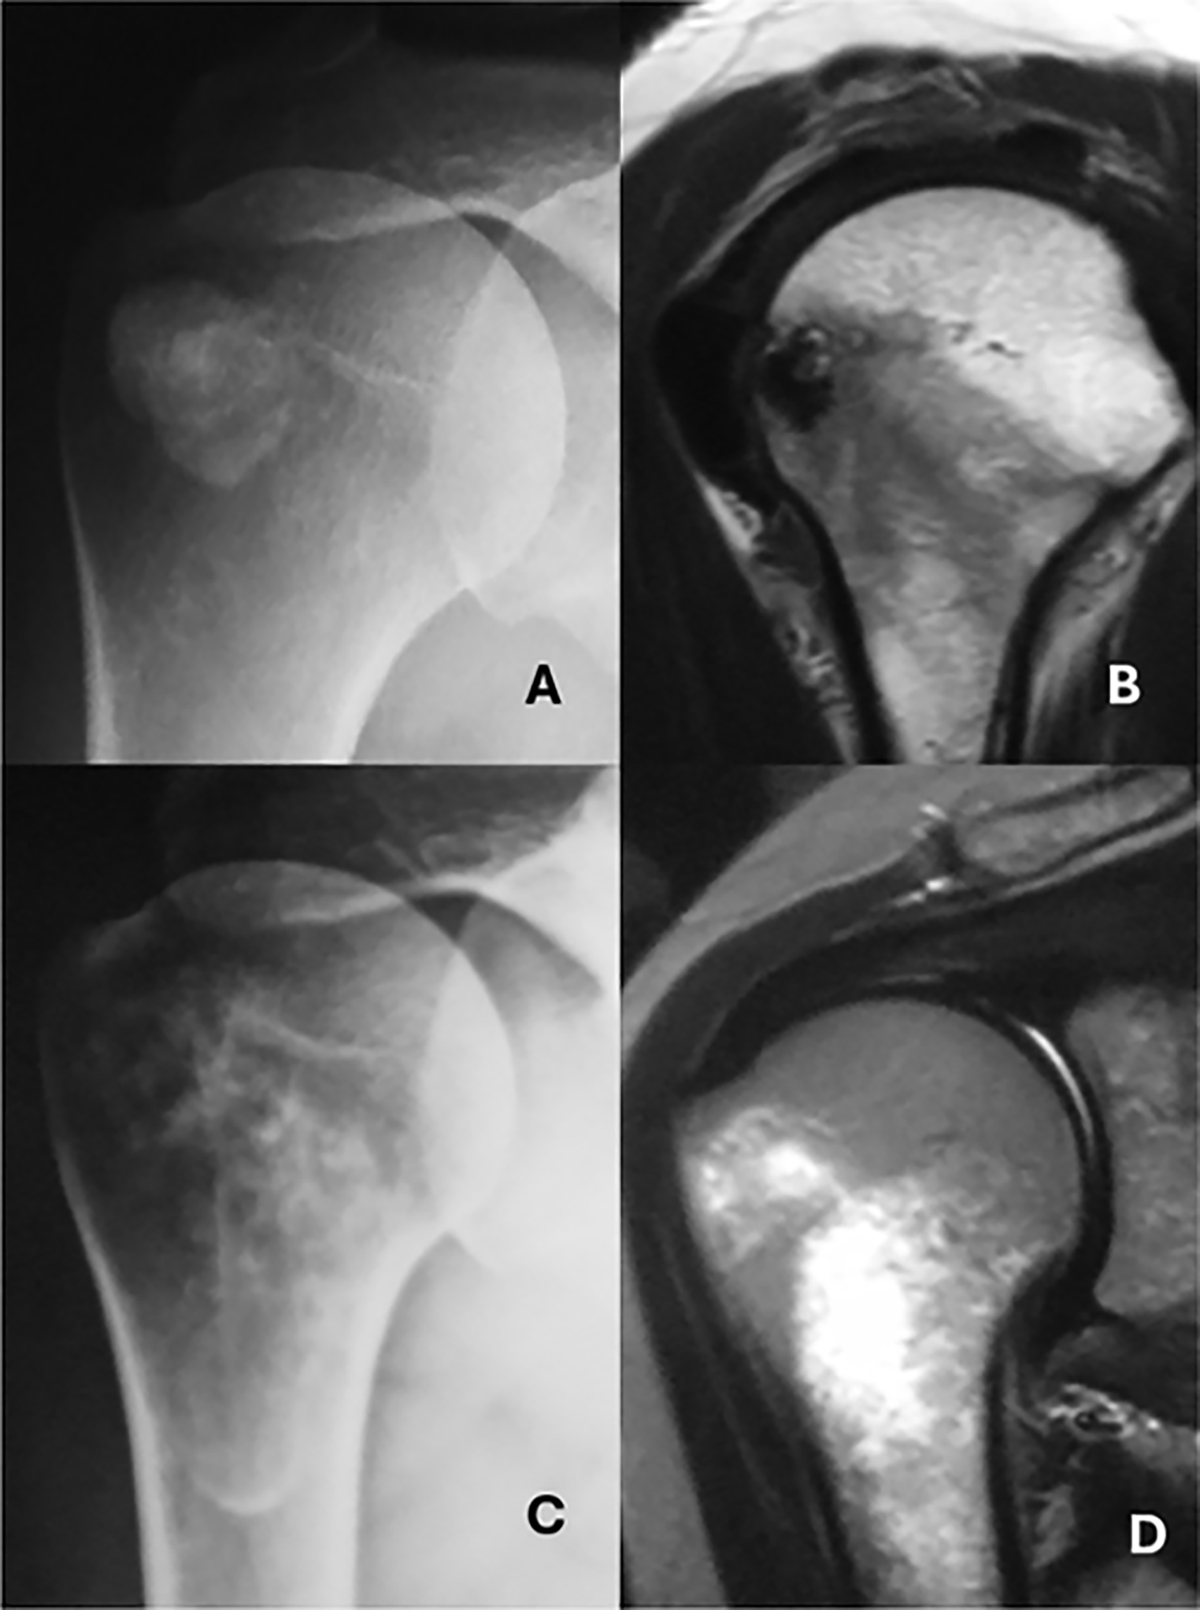

A. AP view showing a calcification located in the tendon of the infraspinatus muscle. B. Oblique sagittal MRI view showing the calcification and the intraosseous deposit. C. Anteroposterior (AP) radiographic image showing extension to the medullary canal of the humerus D. MRI coronal view highlights intramedullary extension.